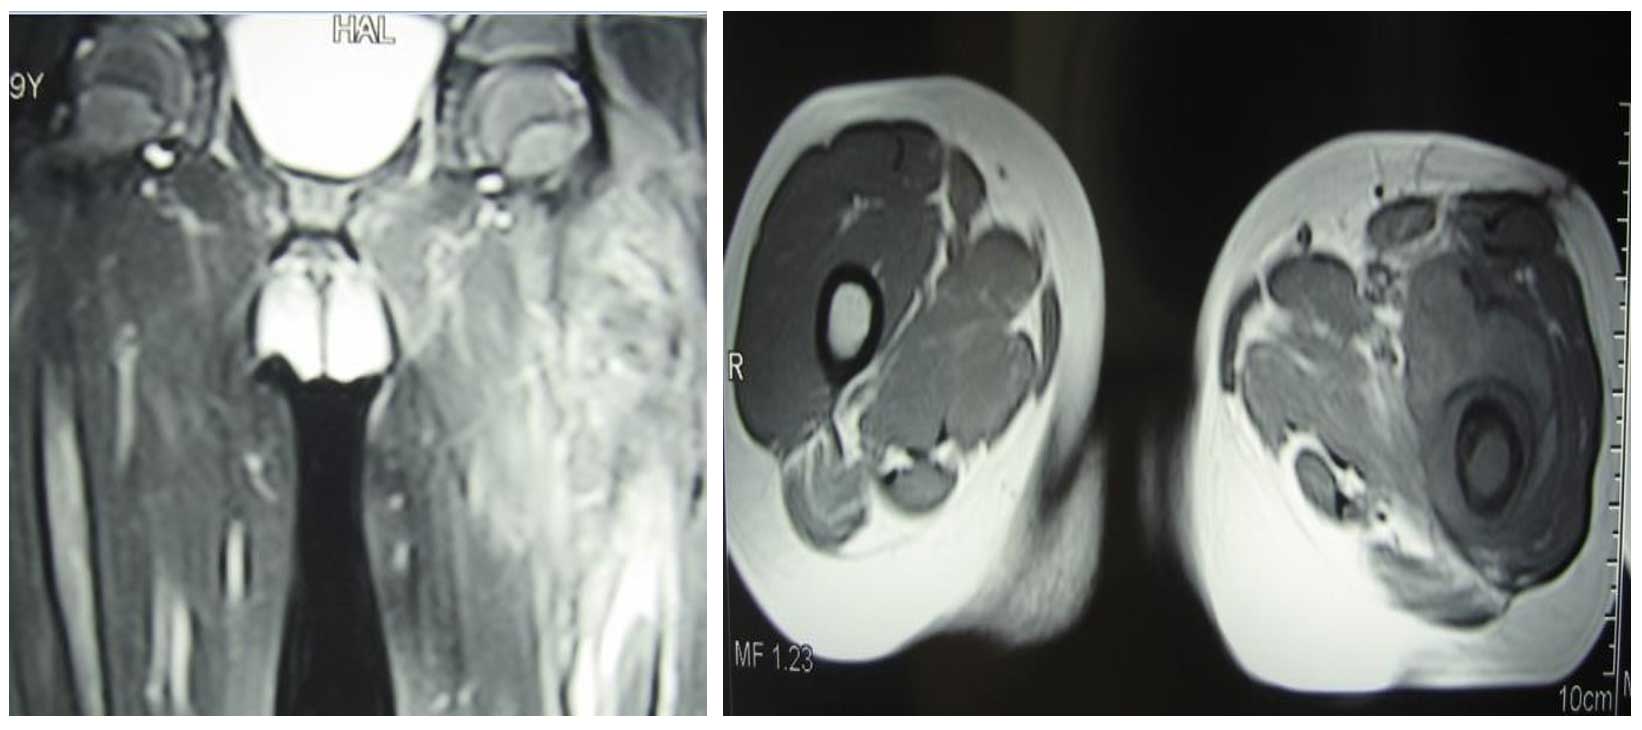

Ameliyat Öncesi: MR’da çevreleyen yumuşak doku kitlesi ve ödem görülmekte.